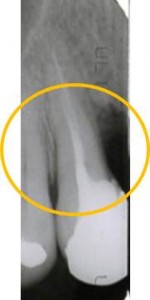

まずエックス線所見です。○で囲んだ部分に骨吸収が認められます。

被せ物を外して土台の状態です。歯周ポケット検査は、手前(8mm、9mm)と奥側(5mm、5mm)です。要は、歯と歯の間から歯周病が進行してしまっています。